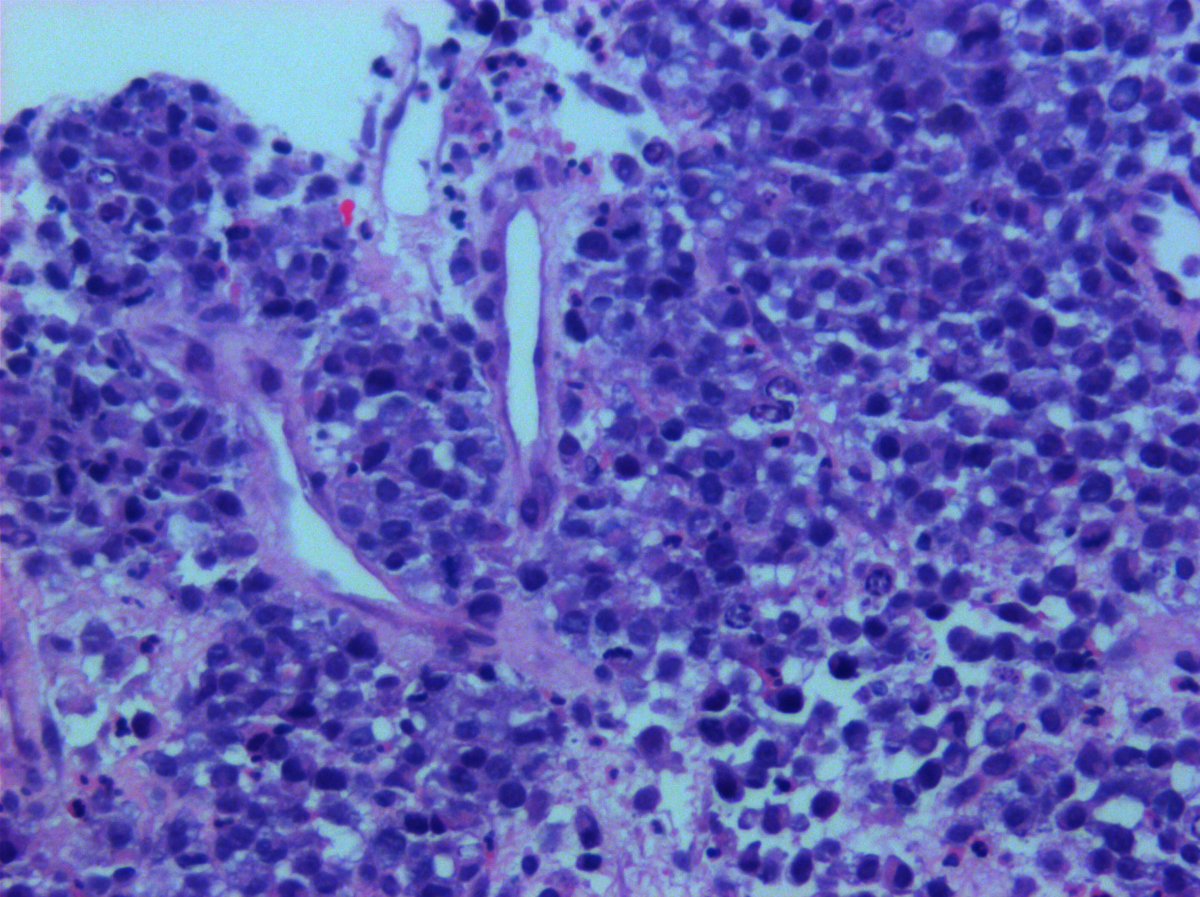

@KukMariya Myelolipomas are clonal. I published this a million years ago.

Hey Pathology twitter! Thoughts?